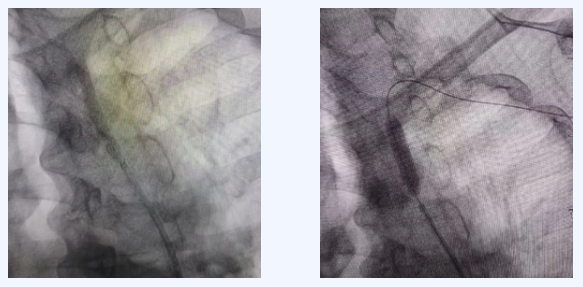

为明确诊断并制定治疗方案,神经内科与介入科医生团队迅速开展联合会诊,一致认为介入治疗是首选方案。随后,由独建库主任在DSA(数字减影血管造影)引导下,成功为患者实施了介入手术。

• CTA或DSA(血管造影):可清晰显示血管狭窄的位置和程度,是诊断的金标准。

目前临床上常用的微创方法。医生通过股动脉穿刺,将球囊或支架送至狭窄处,扩张并支撑血管,恢复血流通畅。该方法创伤小、恢复相对较快。